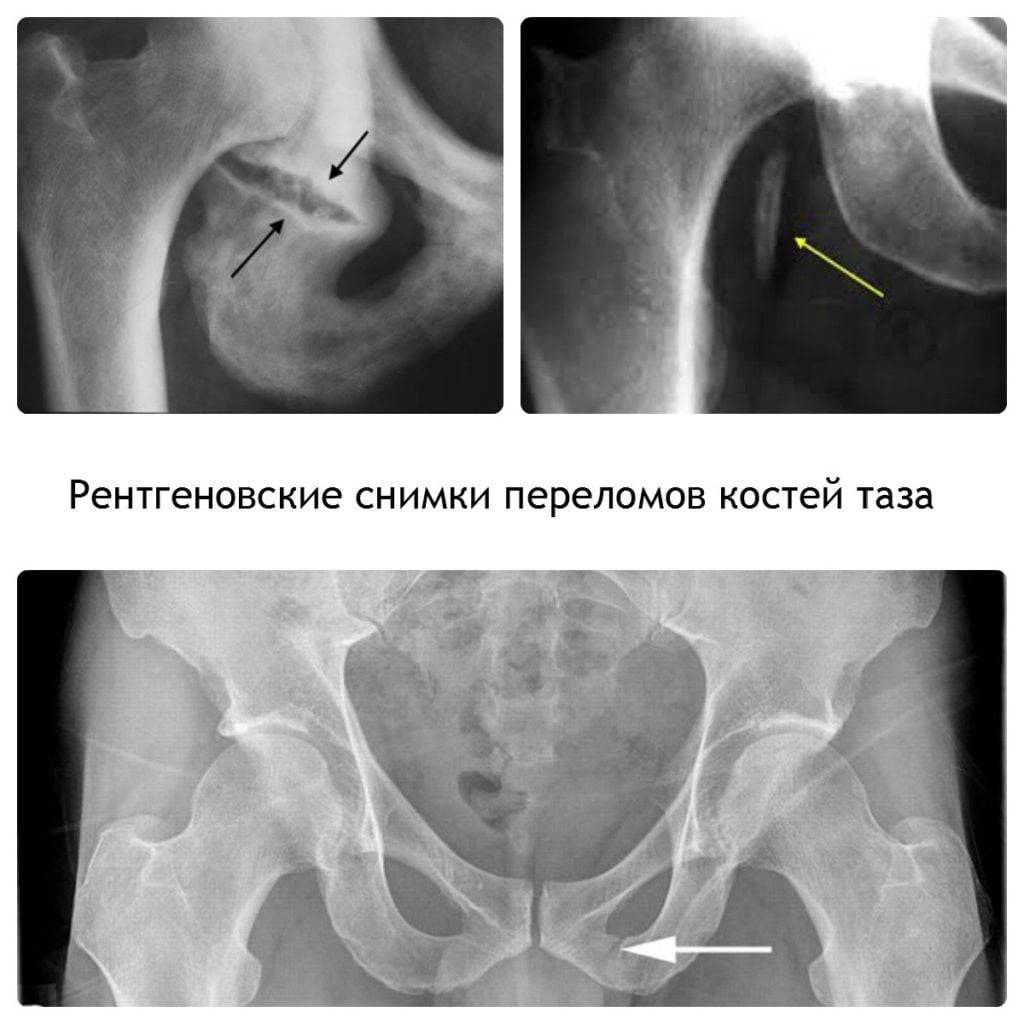

- Рентген позвоночника, желудка, кишечника, почек. Выявляет остеохондроз, непроходимость кишечника, опухоли желудка, мочекаменную болезнь. Для подтверждения кишечной непроходимости выполняют рентген с контрастом.

Переломы позвонков

Перелом позвонков – серьезная травма опорно-двигательного аппарата, которая требует продолжительного и комплексного лечения. Нарушения целостности костной ткани происходит из-за внешнего воздействия (сильный удар, падение с высоты и т.д.) и проявляется в первую очередь болевым синдромом.

Его особенности зависят от степени и локализации повреждения, но чаще всего болевой синдром интенсивный, опоясывающего характера, сопровождается неврологическими нарушениями – нарушениями чувствительности в конечностях, головные боли и т.д.